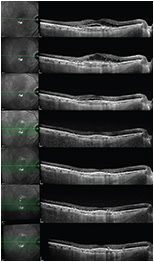

If we instead identify persistent exudative signs on OCT, we might consider switching the anti-VEGF agent and monitoring the anatomical response to the new treatment, perhaps also with a shorter treatment interval (Figure 3).

Figure 3. This sequence of OCT scans shows the evolution of type 1 CNV with subretinal fluid and CME at baseline (OCT scan at top). Four weeks after the last of three monthly injections of ranibizumab, increasing CME was seen (second OCT scan). The patient was switched to aflibercept, and a short follow-up visit was scheduled in two weeks, at which optimal resolution of CME was observed, with recurrence of subretinal fluid (third OCT scan). However, four weeks after the first intravitreal injection of aflibercept, complete resolution of the exudative changes was noted (fourth OCT scan). Two more monthly injections of aflibercept were performed with optimal response (fifth CT scan). Further extension of the retreatment interval, according to a treat-and-extend regimen, was successful, with no evidence of recurrent fluid at six weeks (sixth OCT scan) or eight weeks (seventh OCT scan).